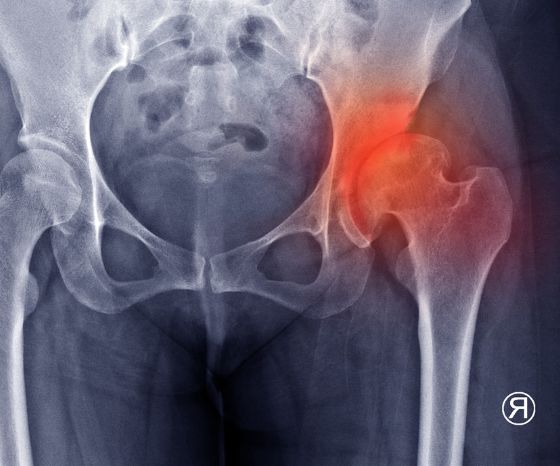

Σύμφωνα με τους Felson et al. (2005 ) Ένα κλασικό χαρακτηριστικό της οστεοαρθρίτιδας είναι οι ιστολογικές αλλαγές στην ποιότητα και το πάχος του αρθρικού χόνδρου. Η μείωση του αρθρικού χόνδρου οδηγεί σε υπερτροφία του υποχόνδρινου οστού και σχηματισμό οστεοφύτων στα άκρα των αρθρικών επιφανειών. Μια άλλη συνέπεια είναι η χρόνια φλεγμονή του αρθρικού ιστού. Όλες αυτές οι αλλαγές οδηγούν σε ακανόνιστες αρθρικές επιφάνειες, οστική διόγκωση, πιθανή πάχυνση της αρθρικής κάψας, και τελικά σε ύδρωπα. Η προκύπτουσα μείωση του αρθρικού χώρου είναι ορατή στις ακτινογραφικές εικόνες, γι' αυτό και μιλάμε επίσης για "ακτινολογική οστεοαρθρίτιδα".